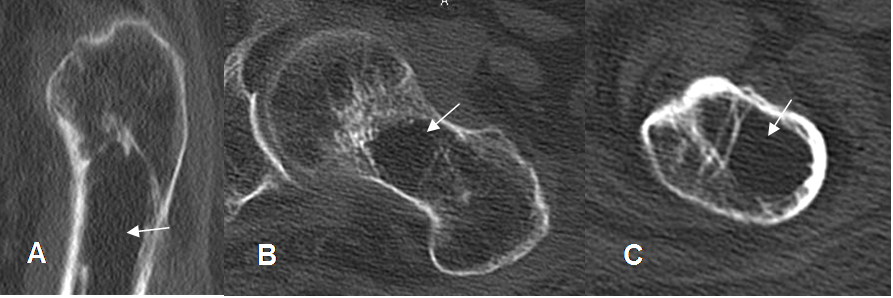

Fig 136. Quiste óseo simple.

A: TAC reconstrucción sagital, B y C: TAC axial. Imagen central de bordes parcialmente definidos, que reemplaza le medular del tercio proximal del fémur y corresponde a quiste simple.